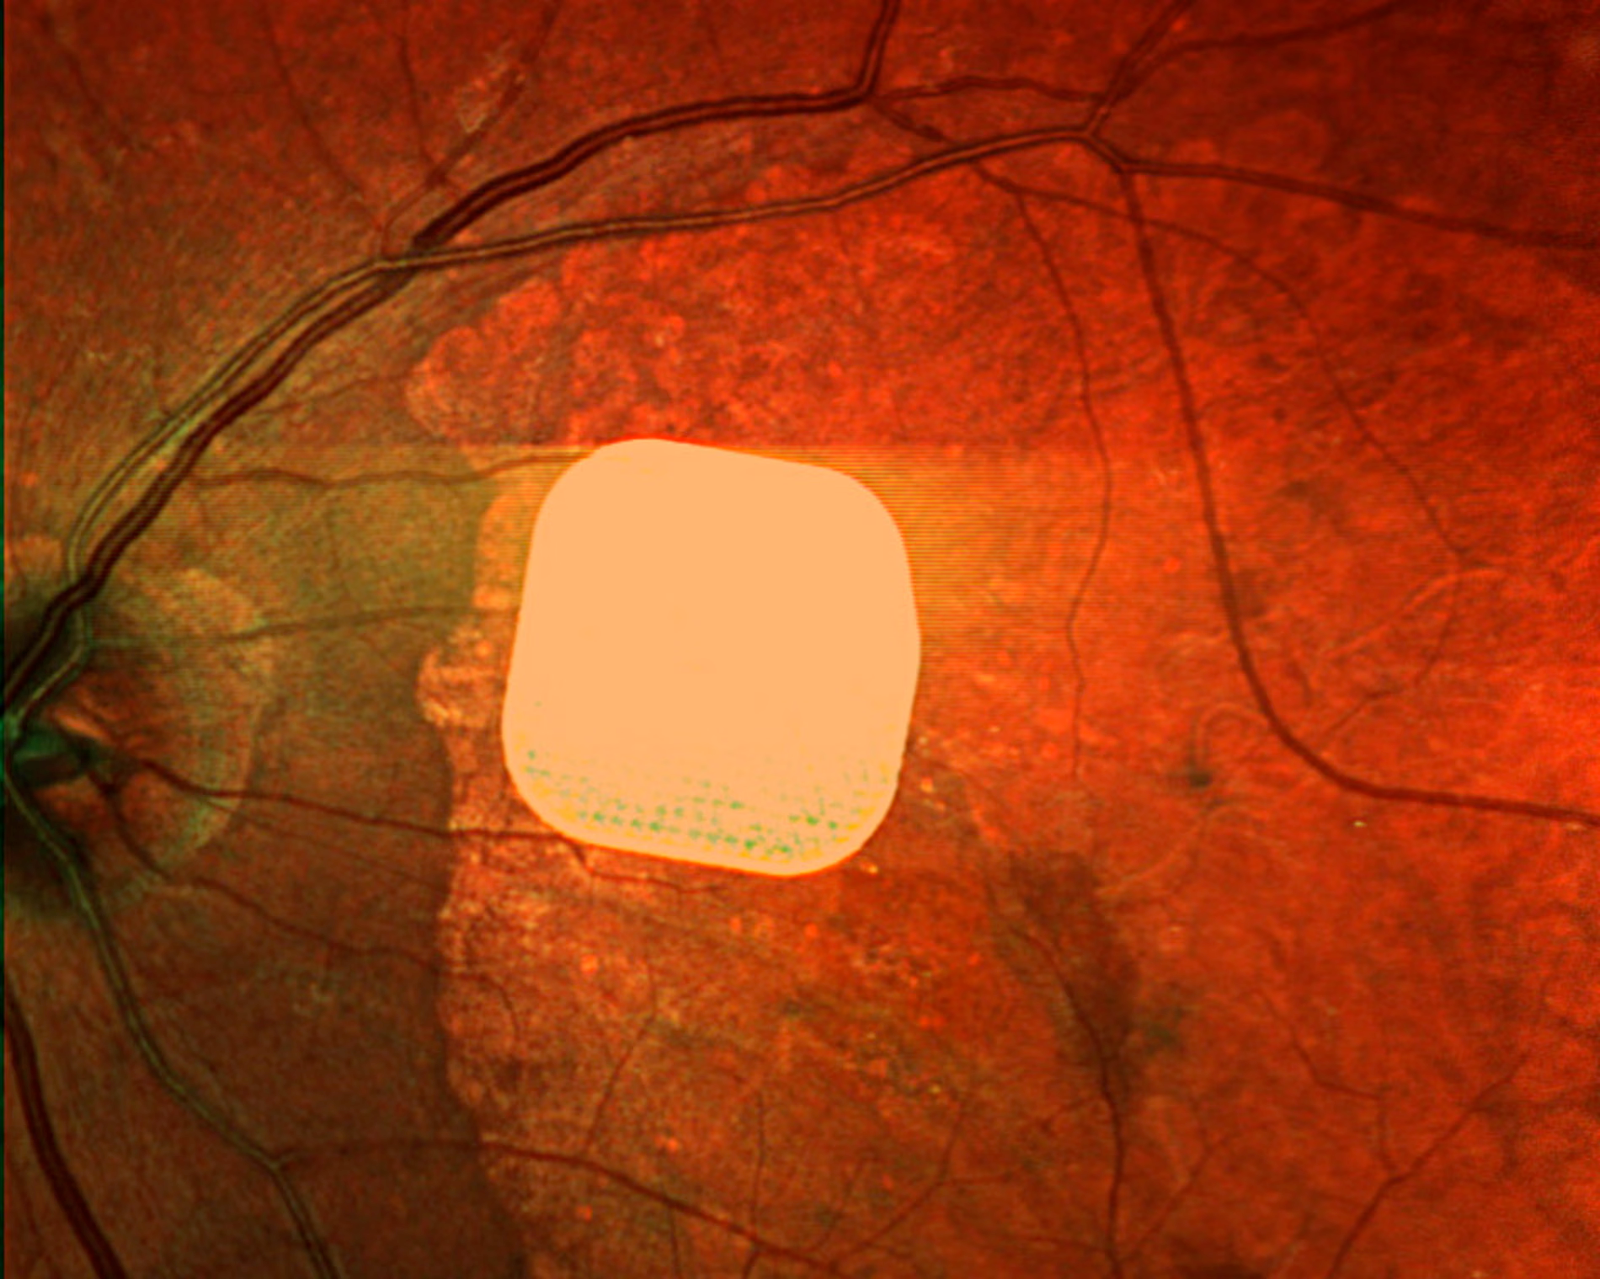

نجحت تجربة طبية جديدة في استعادة البصر لدى 84% من المصابين بالضمور البقعي المرتبط بالعمر (AMD) باستخدام جهاز Prima الإلكتروني، وهو شريحة دقيقة تبلغ حجمها نصف سمك شعرة الإنسان.

- Prima عبارة عن شريحة صغيرة جدًا (2 مم × 2 مم) تُزرع تحت مركز شبكية العين في عملية قصيرة.